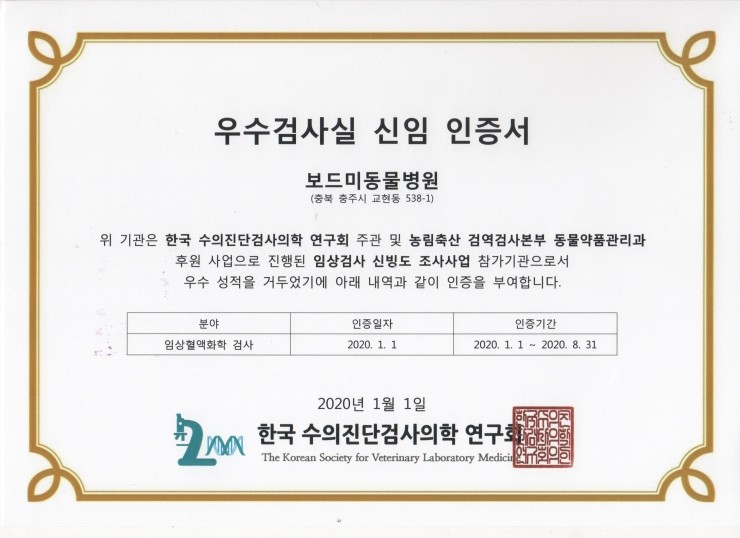

임상혈액화학 검사 분야 우수 성적 인증 (2020)